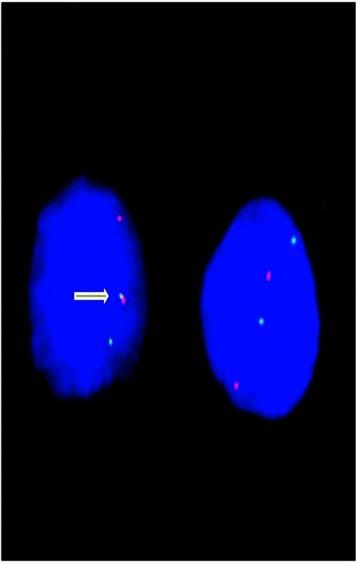

Total DNA was extracted from paraffin-embedded tissues from 45 biopsies of oncocytic tumors. High-resolution melting was used for mutation screening of mitochondrial complex I subunits genes. Specific nuclear rearrangements were investigated by RT-PCR (RET/PTC) or on isolated nuclei by interphase FISH (PAX8/PPARγ). Recurrent point mutations were analyzed by direct sequencing.

In our oncocytic tumor samples, we identified rare TP53 mutations. The series of analyzed cases did not include poorly- or undifferentiated thyroid carcinomas, and none of the TP53 mutated cases had significant mitotic activity or high-grade features. Thus, the presence of disruptive TP53 mutations was completely unexpected. In addition, novel mutations in nuclear-encoded complex I genes were identified.